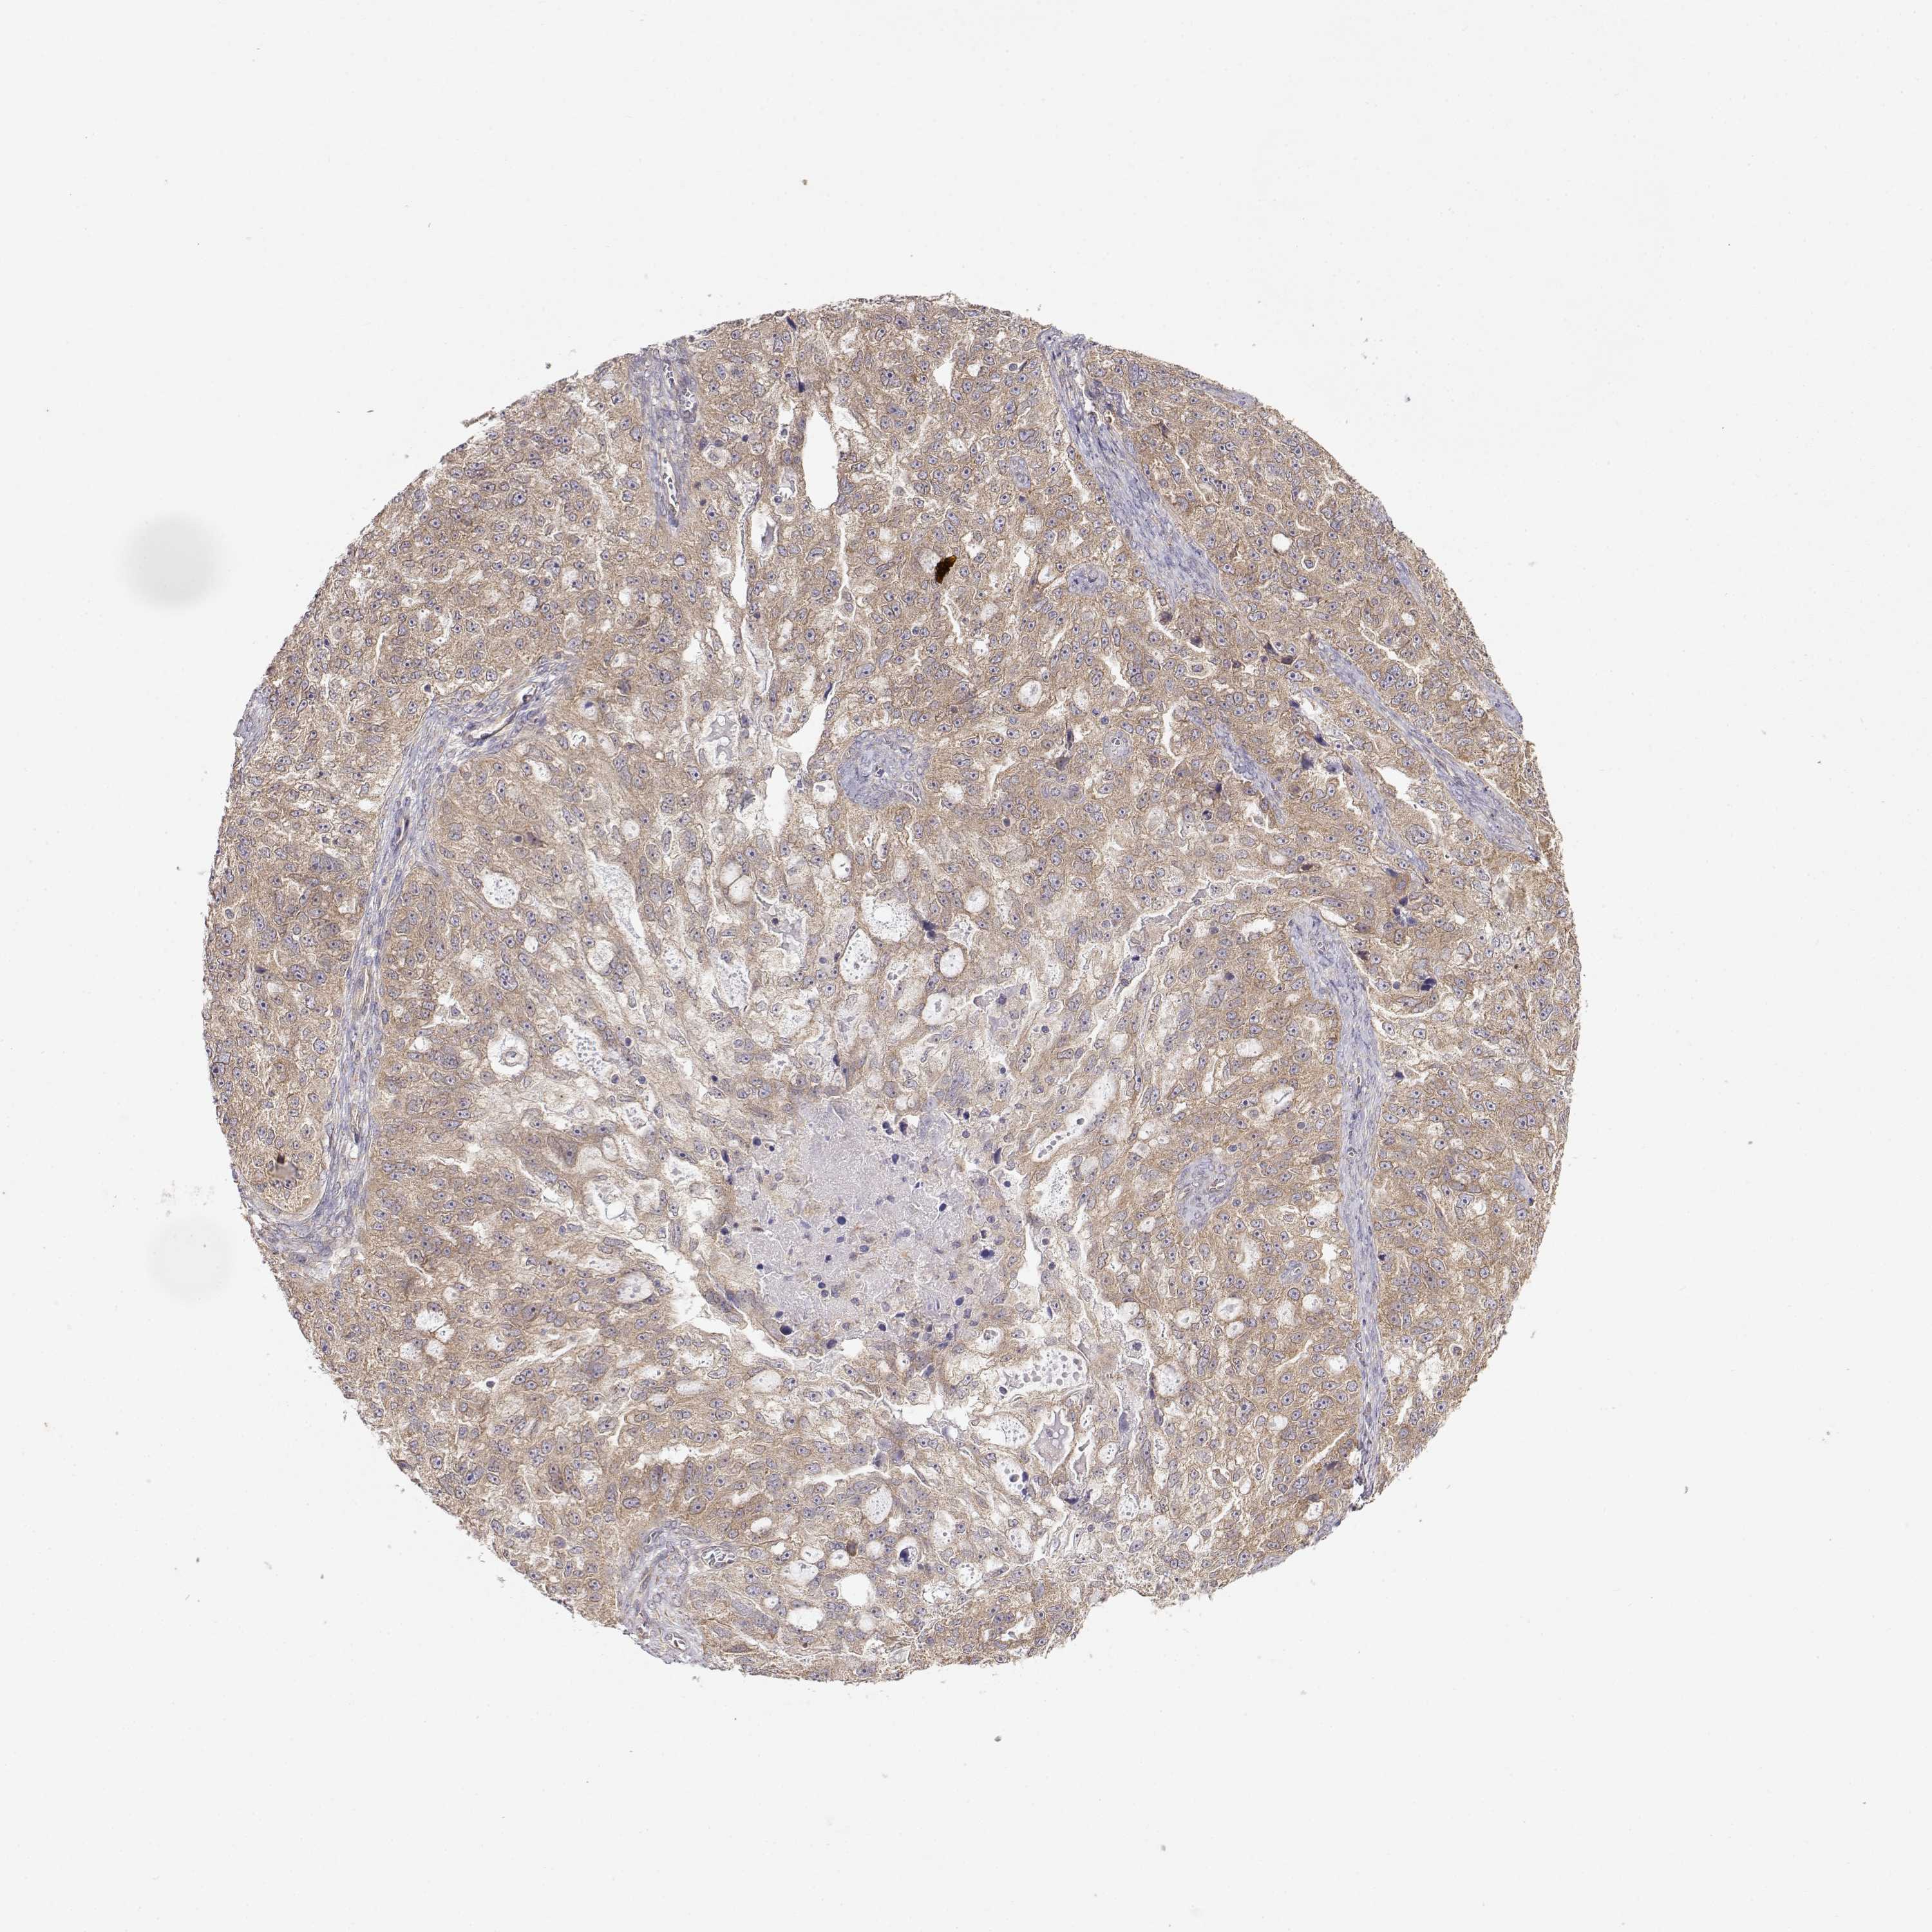

OVARIAN CANCER - Protein expressioni

A mouse-over function shows sample information and annotation data. Click on an image to view it in a full screen mode. Samples can be filtered based on level of antibody staining by selecting one or several of the following categories: high, medium, low and not detected. The assay and annotation is described here.

Note that samples used for immunohistochemistry by the Human Protein Atlas do not correspond to samples in the TCGA dataset.

Antibody stainingi

Antibody staining in the annotated cell types in the current human tissue is reported as not detected, low, medium, or high, based on conventional immunohistochemistry profiling in selected tissues. This score is based on the combination of the staining intensity and fraction of stained cells.

Each image is clickable and will lead to virtual microscopy that enables deeper exploration of all samples and also displays staining intensity scores, fraction scores and subcellular localization as well as patient and tissue information for each sample.

Antibody HPA073653

Cystadenocarcinoma, serous, NOS

Cystadenocarcinoma, mucinous, NOS

Carcinoma, endometroid